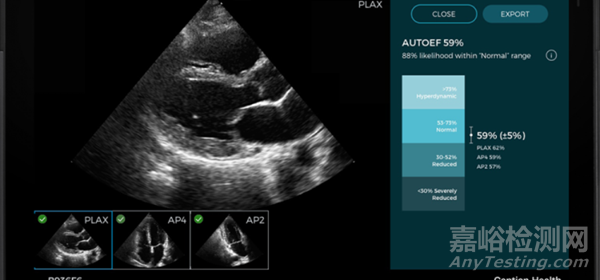

人工智能應(yīng)用程序?qū)⒓傻皆摴镜?EPIQ CVx 和 Affiniti CVx 超聲系統(tǒng)中,通過成熟的人工智能技術(shù)幫助加快心臟超聲分析速度。

而飛利浦通過將人工智能集成到超聲心動圖解決方案中,現(xiàn)在可以自動化一些步驟來支持臨床醫(yī)生的決策,在幾秒鐘內(nèi)更加高效地檢測、診斷和監(jiān)測各種心臟疾病。

傳統(tǒng)上,RWMA的評估依賴于醫(yī)生的主觀視覺分析,這不僅耗時,而且可能存在個體差異。然而,Lang博士的研究顯示,AI算法能夠在短短幾秒內(nèi)完成這一分析任務(wù),提供快速且準(zhǔn)確的結(jié)果,從而顯著提高診斷效率。

這項研究中使用的AI功能,是飛利浦心血管超聲系統(tǒng)的一部分。該系統(tǒng)集成的AI經(jīng)過大量來自真實臨床環(huán)境的匿名患者數(shù)據(jù)集的訓(xùn)練,不僅提升了心臟成像的質(zhì)量和可重復(fù)性,還大幅提高了工作效率。Lang博士的研究表明,通過AI的輔助,超聲心動圖的診斷過程將變得更加高效和準(zhǔn)確,為心臟病患者的早期診斷和治療提供了強有力的工具。